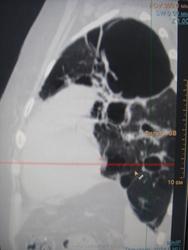

Больная с 03 года выявлена с диагнозом ФКТЛ. Ведет асоциальный о  браз жизни, лечится по настроению. На снимках- одни страсти и таких живучих больных- хроников уже мало. Абацилирована с 06года, если бы высевала, ведя такой образ жизни, давно бы сгинула.

Да, по всей видимости, на обычных рентгенограммах, возможно и томограммах, картинка весьма напоминает фиброзно-кавернозный туберкулёз, который, как трактует фтизиатрия относится к запущенным формам туберкулёза, за который ох как сильно бьют!

Не могу сказать, что видел сильно много ФКТ, но видел..., а представленный случай, на мой взгляд ФКТ не "пахнет". При таких то полостищах, а может быть и кистах слева, довольно интеллигентная картинка справа...

особенности патологической анатомии туберкулеза, сочетающегося с кистозной гипоплазией легких был изучен выдающимся русским патологоанатомом, антропологом, биологом В.Г.Штефко. 100-летие В.Г.Штефко было отмечено в 1993 году.  В.Г. Штефко считал, что  дегенеративные легкие особенно восприимчивы к туберкулезной инфекции. Мнение В.Л. Катенёва ("а дизонтогенетические кисты?") не фантастика. Вероятность того, что туберкулез легких развился на фоне порочного легкого, очень даже высока. Кроме того, отечественными исследователями подробно описано "разрушенное легкое", как исход прогрессирущих форм туберкулеза.

Наш опыт пульмонэктомий по поводу цирротического туберкулеза показал, что у всех больных, оперированных с таким диагнозом, имелся активный хронический деструктивный туберкулез, причем каверны располагались действительно среди цирротичеоки измененной легочной ткани (рис. 13). Это позволяет выделить такой вид цирротического туберкулеза, как каварнозно-цирротический или поликавернозно-цирфотический, тотально поражающий легкое, иначе говоря разрушенное легкое.

В клинической классификации рекомендовано относить такие изменения с наличием каверн, с бронхогенными отсевами и бацилловыделением к группе фибвозно-кавернозного туберкулеза. Однако мы считаем, что для такого процесса, при котором тотально поражено целое легкое с полной потерей его нормальной структуры и функции, более подходящим является название разрушенное легкое. Действительно, здесь мы имеем дело уже не с органом, пусть даже патологически измененным, а с его остатками.

Морфологические и мнкробиологические данные показывают, что при разрушенном легком туберкулезной этиологии речь идет об активном торппдно текущем процессе, сопровождающемся вспышками л диссеминацией. В цирротической ткани, окружающей каверны, расположены уязвимые, ломкие, легко подвергающиеся аррозии сосуды, что является основой кровохарканий и профузных кровотечений.